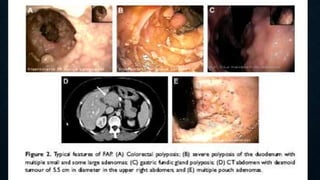

POLIPOSIS ADENOMATOSA

FAMILIAR

• Trastorno hereditario autosomico dominante. Penetrancia del 100%.

• 80% hay antecedentes familiares.

• 10-30% mutaciones nuevas.

• 1/10000 nacidos vivos.

• Edad promedio en detectar los pólipos es 15 años.

• 15% evidencia de pólipos a los 10 años.

• 75% evidencia a los 20 años.

• 90% evidencia a los 30 años.

• El CG. Aparece en promedio a los 35 años.

POLIPOSIS

ADENOMATOSA FAMILIAR

• Los pólipos pueden tapizar toda la superficie del epitelio en casos severos y dejar

indemne algunas porciones del epitelio.

• La mayoría mide menos de 5 y 10 mm.

• El hallazgo de uno o más pólipos de más de 1 cm. se asocia a 47 % de padecer

Cancer.

• La frecuencia de neoplasias sincrónicas o metacrónicas es elevada.